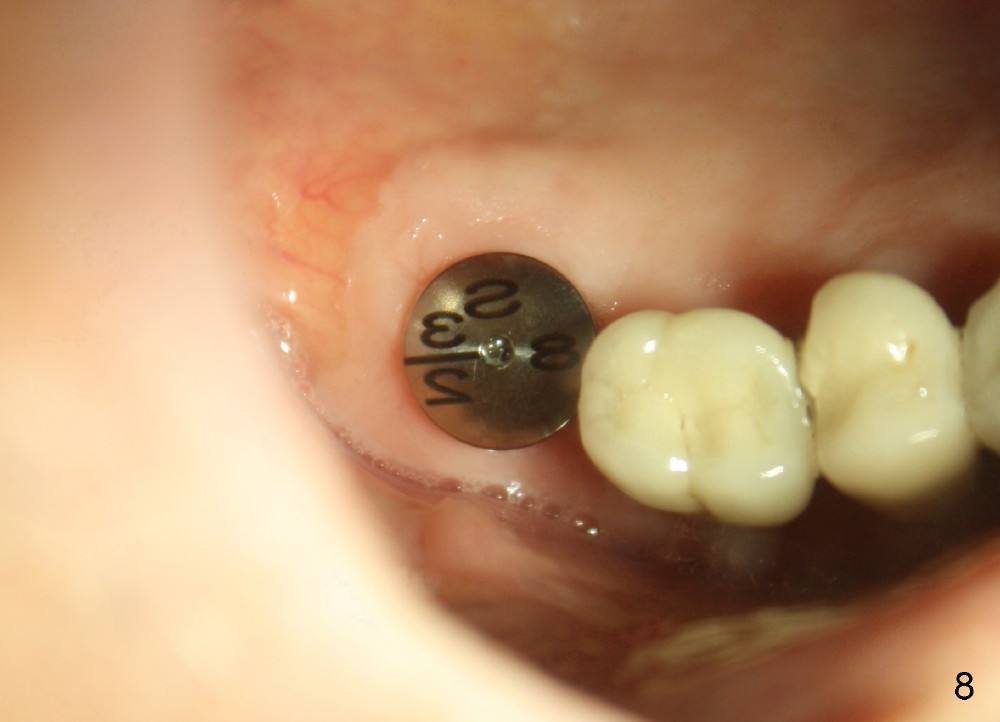

Analysis of preop PA suggests that the density of the cancellous bone is low at the site of the tooth #2. It is confirmed when a 2 mm pilot drill is used to initiate osteotomy. There is no drilling resistance once the pilot drill penetrates the cortex. A parallel pin is inserted for trajectory (Fig.1: P; 8 mm deep). The osteotomy is slightly moved distally with Lindermann bur and enlarged by inserting Bone Expanders from 2.6 to 3.8 mm at the depth of 12 mm (Fig.2). The osteotomy is then intended to move mesially and the depth is increased to 14 mm. Finally a 5.3x14 mm submerged implant is placed with insertion torque ~ 40 Ncm (Fig.3). The implant looks to have been tightly engaged into the bone (Fig.4). In one word, minimal bone removal is required for implant placement in the soft bone, particularly in the maxillary posterior region. A 8.2 mm healing abutment is placed; the flaps are closed by Chromic gut suture and perio glue (Fig.5). The wound heals normally 1 week postop (Fig.6). Fig.7 shows X-ray 3 months postop (H: healing abutment). Soft tissue looks healthy 4 months postop before (Fig.8) and after (Fig.9) removal of the healing abutment for restoration. There is no bone loss 7 months post cementation and 11 months postop (Fig.10 C: crown). It appears that bone expansion prevents bone resorption. There is no bone resorption 1 year 9 months post cementation. The implant is functioning 3 years 9 months post cementation (Fig.11).